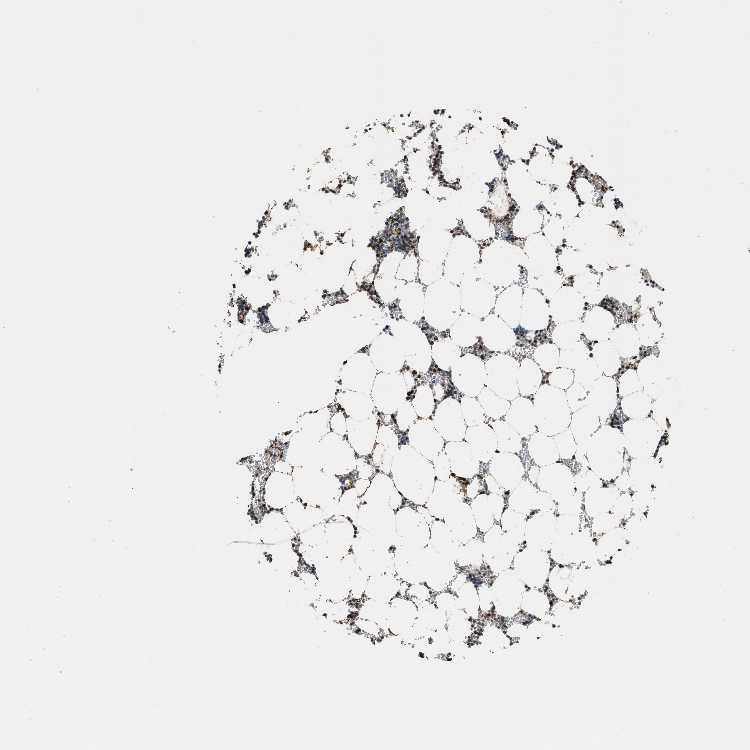

TISSUE PRIMARY DATA BONE MARROW Show tissue menu

BONE MARROW - Antibody stainingi

Antibody staining in the annotated cell types in the current human tissue is reported as not detected, low, medium, or high, based on conventional immunohistochemistry profiling in selected tissues. This score is based on the combination of the staining intensity and fraction of stained cells.

Each image is clickable and will lead to virtual microscopy that enables deeper exploration of all samples and also displays staining intensity scores, fraction scores and subcellular localization as well as patient and tissue information for each sample.

Antibody HPA019522Antibody HPA021002

Hematopoietic cells LowHigh